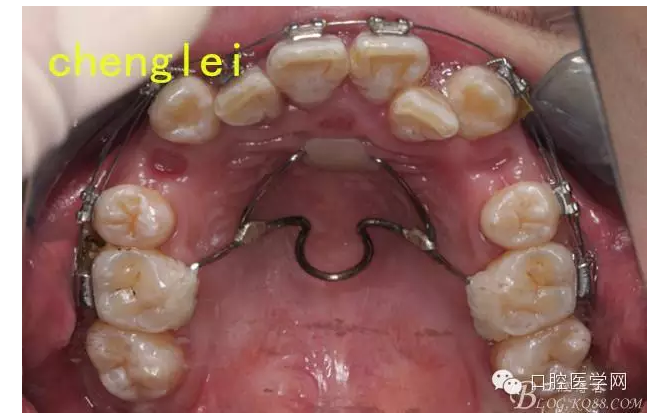

于是為了節(jié)約患者的大量時(shí)間,和選帶環(huán)的繁瑣,故采用粘接式的簡(jiǎn)易腭桿加nance托。主弓絲為1.0鋼絲,輔弓絲為0.8,之后完成焊接 ,打磨。關(guān)于增強(qiáng)支抗抗的手段,武廣增老師習(xí)慣應(yīng)用腭桿和nance 托,效果很好,華西的趙志河老師也強(qiáng)調(diào)過腭桿增強(qiáng)支抗,控制磨牙前移的作用有限,不過nance托可以達(dá)到中強(qiáng)支抗。為了達(dá)到良好的效果。

由于想法的構(gòu)思,患者沒有當(dāng)天戴用,而是,三天以后,約患者過來試戴,圖中可以看出,筆者的nance托并沒有制作,而是空了出來,因?yàn)閚ance托的關(guān)鍵,在于與粘膜密貼,而且不能用力壓迫粘膜,又加上 是粘接式的操作,所以為了考慮操作的準(zhǔn)確,密合,得當(dāng),所以,決定在口內(nèi)粘接完成以后,采用補(bǔ)牙樹脂,用手搓成一個(gè)小球,壓在nance弓的鋼絲上,成一個(gè)小圓餅狀,就成為了一個(gè)nance托,這樣的方法達(dá)到了的粘接式nance托與粘膜的密合性,而且口內(nèi)操作,不產(chǎn)熱,采用光固化樹脂完成。還有一個(gè)優(yōu)點(diǎn),完成以后nance托很薄,口感舒適。還有一個(gè)操作時(shí)間很短,患者進(jìn)行粘接試戴,到完成只有10分鐘。